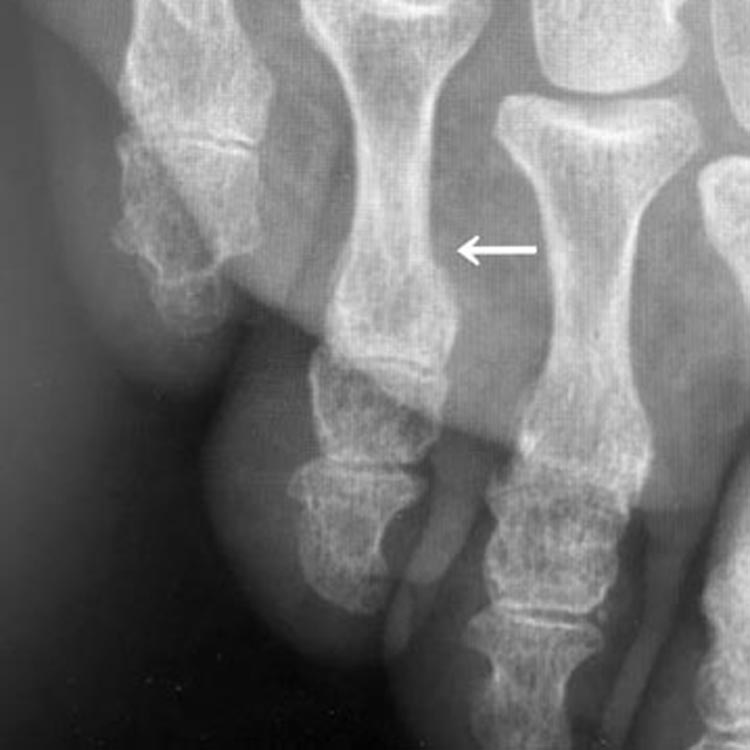

受傷3週後のレントゲン写真

受傷3週後(矢印が新しい骨がかなりできています。この時点で固定を終了しました。)